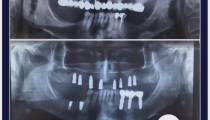

انجام 15 واحد ایمپلنت